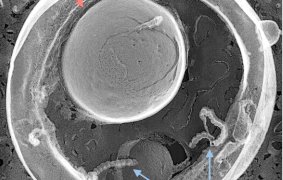

The transmembrane serine protease 2 (TMPRSS2) plays a critical role in SARS-CoV-2 infection by priming the viral Spike (S) protein for host cell entry and thus represents a potential target for COVID-19 therapy. Here monoclonal antibodies (mAbs) against human TMPRSS2 were established for therapeutic application. In vitro infection by SARS-CoV-2 of cell lines and human lung organoids was strongly inhibited by the TMPRSS2 mAbs. These mAbs inhibited infection of all SARS-CoV-2 variants tested including omicron. mAbs recognized epitopes different from the enzymatic active site and did not inhibit protease activity, suggesting blockade of steric interactions of S protein-ACE2/TMPRSS2. The inhibitory activity of the mAbs in vivo was examined in human ACE2/TMPRSS2-double knock-in mouse and macaque models. Analysis of viral titers and histopathological analysis of the lung in these infected animals indicated that the TMPRSS2 mAb effectively suppressed viral titers and induction of inflammation in vivo.